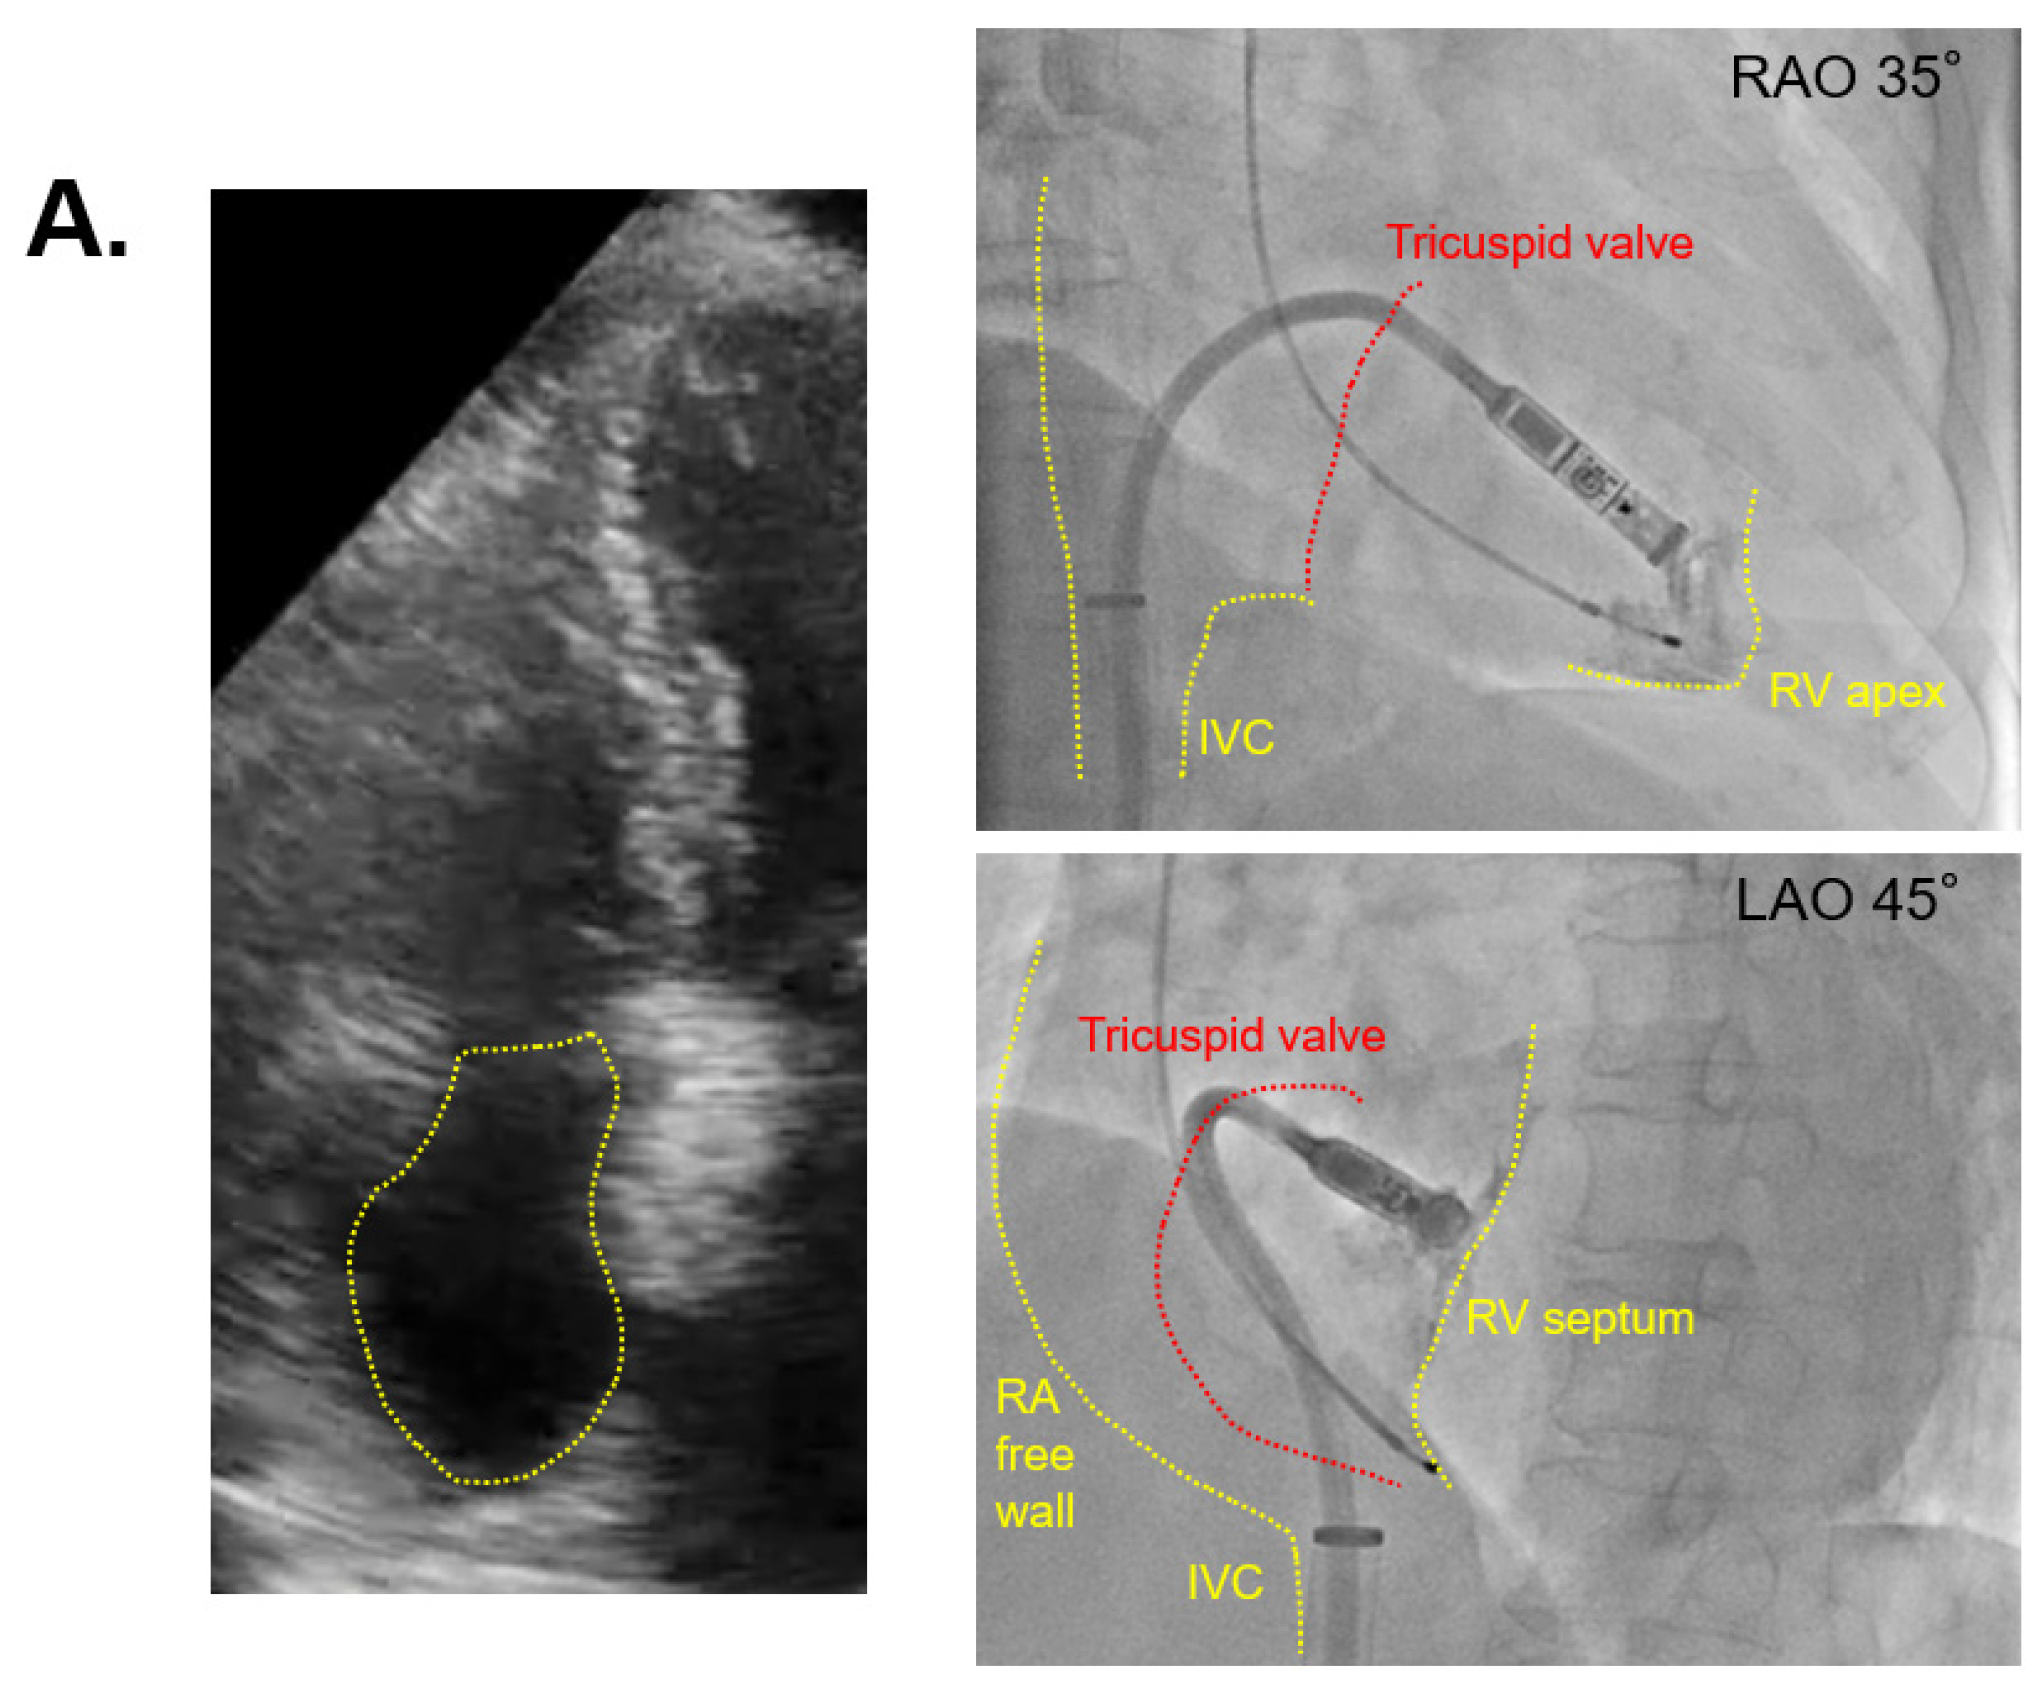

The two cases with the shortest and longest procedure times are displayed in Figure 3A,B, respectively. The patient of Figure 3A had a smaller right atrium with 3.3 cm right atrial diameter and 14.7 cm2 right atrial area, and a procedure time of 30 min. The patient of Figure 3B had a larger right atrium with 4.3 cm right atrial diameter and 24.7 cm2 right atrial area, and the procedure time was 185 min (Figure 3B).

Figure 3.

Echocardiography in the shortest and longest procedures. (A) The case of smaller right atrium with 30 min of procedure time; (B) the case of larger right atrium with 185 min of procedure time; echocardiographic views indicate four chambers, viewing from the apex, and yellow dashed lines indicate the right atrium; IVC = inferior vena cava, RV = right ventricle.